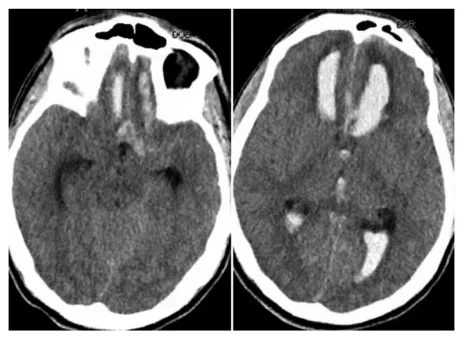

当动脉瘤破裂,血液首先涌入蛛网膜下腔(SAH);若出血迅猛,更可能突破蛛网膜,在硬脑膜下形成巨大的血肿(SDH)这场二次打击来势汹汹,患者的生存希望究竟几何?INC国际神经外科医生集...